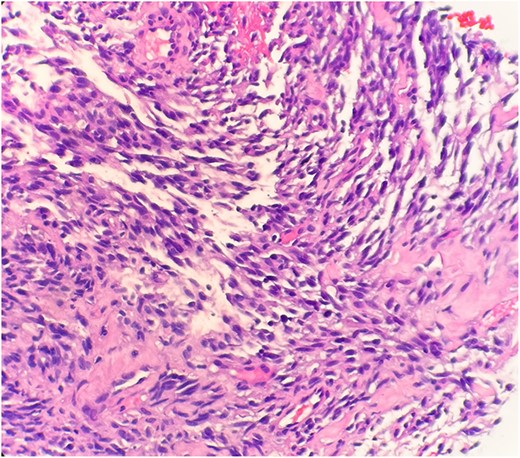

The pathological sections taken from the mass demonstrated spindle-tumor cells within a focal sclerotic and myxoid stroma with increased mitotic activity; no necrosis was visualized (Fig. 1). The vessels from the pleural mass showed a staghorn-like appearance. Tumor cells biopsied from the lung mass were positive for vimentin and CD10, as well as biomarkers for sarcomatoid mesothelioma: WT1 and D2–40 (Fig. 2). The tissue sample was negative for immunostains keratin and calretinin, which is unusual for mesothelioma. The lung mass biopsy was also negative for cytokeratin (CK) and PAX8, which ruled out the possibility of metastatic RCC. Due to the visualization of staghorn-appearing vessels, malignant solitary fibrous mesenchymal tumor was considered as well but was ruled out due to lack of STAT6 expression.

Immunohistochemical stain reveals that tumor cells are positive for WT-1 (IHC stain x40).